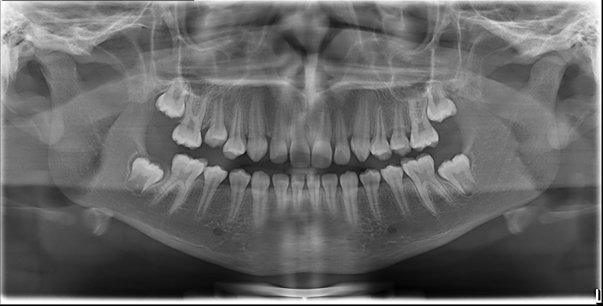

Panorâmica Digital